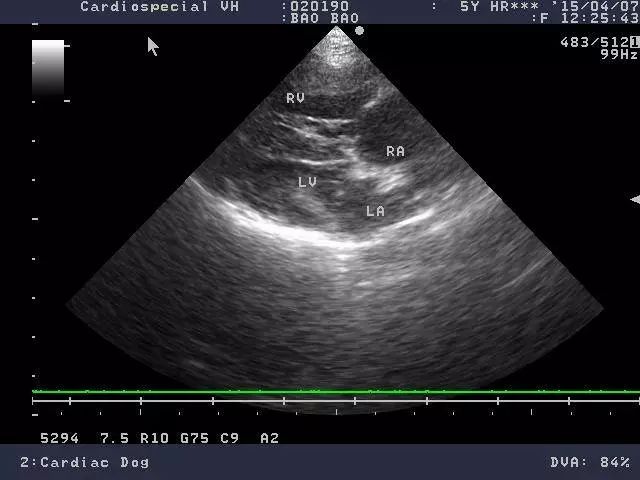

心丝虫病是最常见的诊断方式是检测血液中是否有心丝虫存在。许多宠物医院都可以进行检测,几分钟内就能得到结果。根据检测结果和动物的症状,还可以进行心脏超声检查来确定是否感染和感染的严重程度。